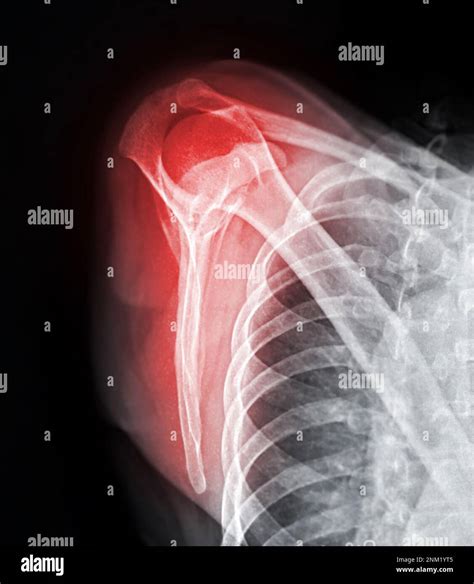

• Fractures: Breaks in the bones of the shoulder, such as the humerus, scapula, or clavicle.

• Dislocations: When the head of the humerus is forced out of the shoulder socket.

Interpreting X Ray Shoulder Joint results requires a trained eye. Radiologists look for specific signs and abnormalities that indicate various conditions. Some key points to consider include:

• Bone Density: Changes in bone density can indicate conditions like osteoporosis or bone tumors.

• Fractures: Visible breaks or cracks in the bones.

• Joint Space: The space between the bones can indicate the presence of arthritis or other degenerative conditions.

• Soft Tissue: Although X-rays primarily show bones, they can also reveal certain soft tissue abnormalities.

Radiologists use these findings to make a diagnosis and recommend appropriate treatment options.